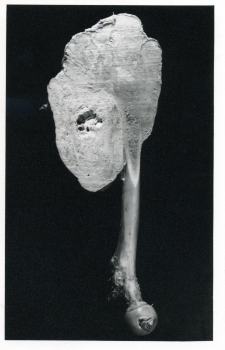

- Periosteal fibroma of the diaphysis of the femur

- An adult right femur, showing a periosteal fibroma of the diaphysis. The knee joint has not been involved and the distal half of the diaphysis is surrounded by a globular tumour. The greater part of this mass is osseous and densely hard, only the proximal segment of the tumour is soft and fleshy. In the immediate neighbourhood of the tumour proximally the bone is normal. Microscopically the tumour is a fibroma of a moderately cellular type enclosing in the portions examined a few fragments of bone. There is no evidence of malignancy.

Height: 44.5 cm

Width: 21.0 cm

Depth: 14.2 cm